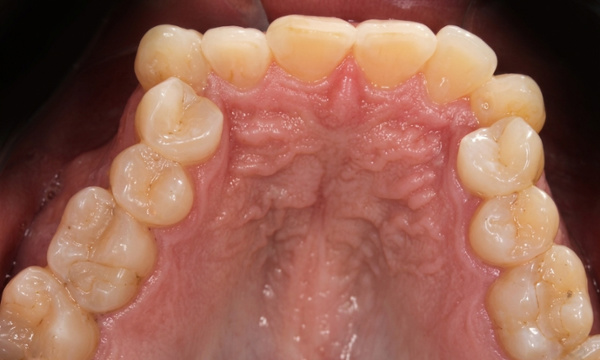

Orthodontic treatment for adults often involves managing complex dental histories. This patient in his 40s presented with a collapsed, square-shaped maxillary arch, a crossbite, and shifted midlines. Complicating the case were congenitally missing lower second premolars and over-retained primary first molars. Under the specialized care of Dr. Jesus Martinez, we utilized Rapid Palatal Expansion (RPE) to restore proper arch width and traditional braces to correct the alignment and bite. Strategic management of the primary teeth and missing permanent teeth allowed us to achieve a stable, functional result secured with fixed retainers. We invite you to schedule a personal evaluation at our concierge Miami or Kendall offices, where the specialist evaluates every case personally from start to finish.